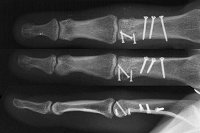

The joint was reconstructed with 1.0mm screws and the shaft fixed with 1.3mm screws using the Synthes titanium modular hand tray.

Intraoperative fluoroscopy.